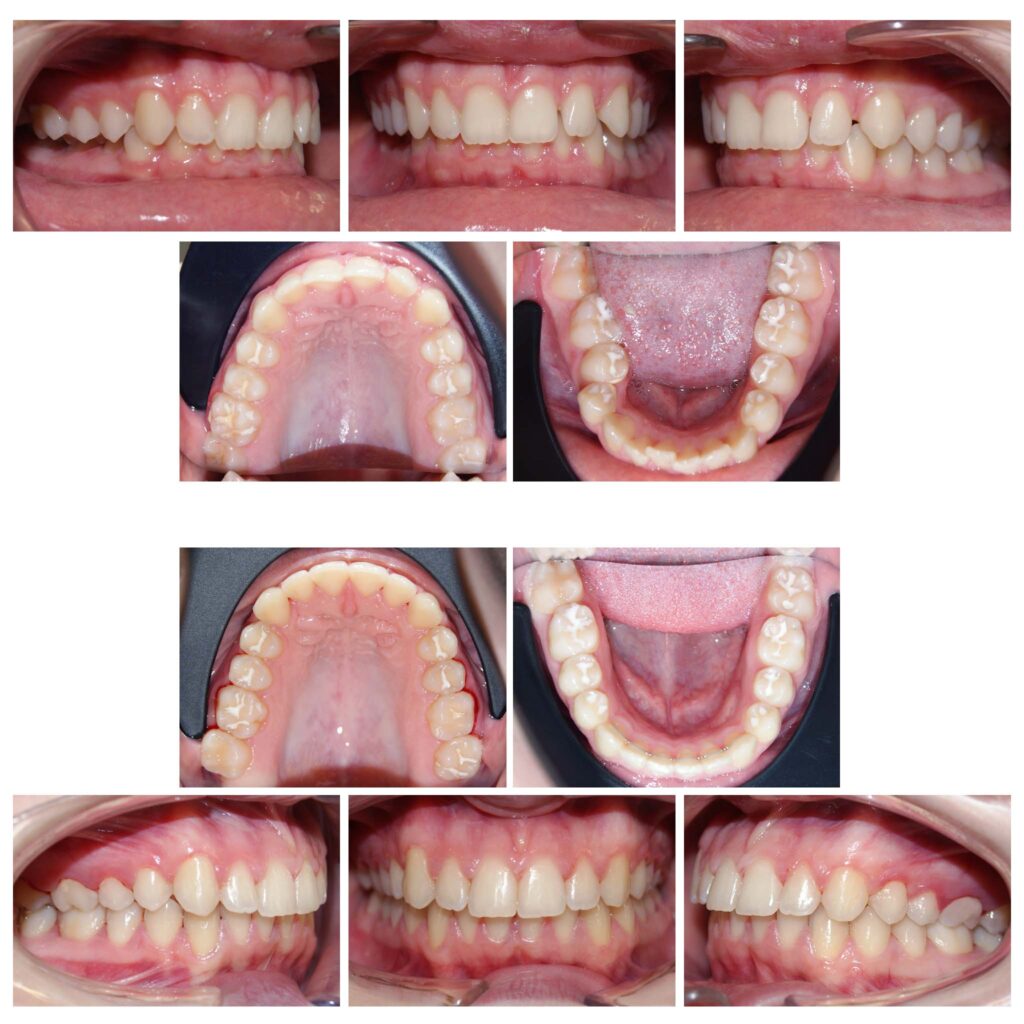

Corectarea angulațiilor dentare și a mușcăturii

Îndreptarea axelor dentare are un efect semnificativ atât asupra dinților cât și asupra țesuturilor de susținere

Pentru că detaliile fac diferența – a se remarca înălțarea și lărgirea zâmbetului #contenție fixă